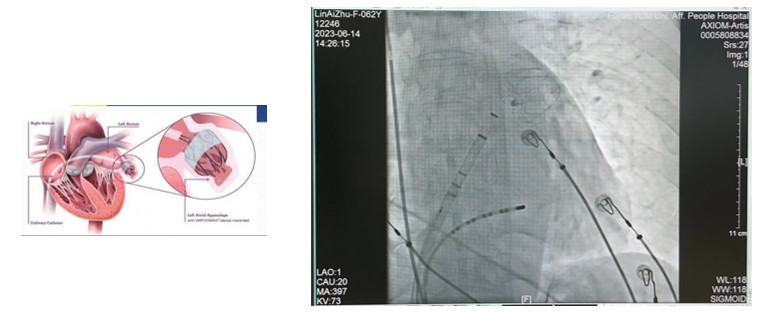

左心耳封堵术